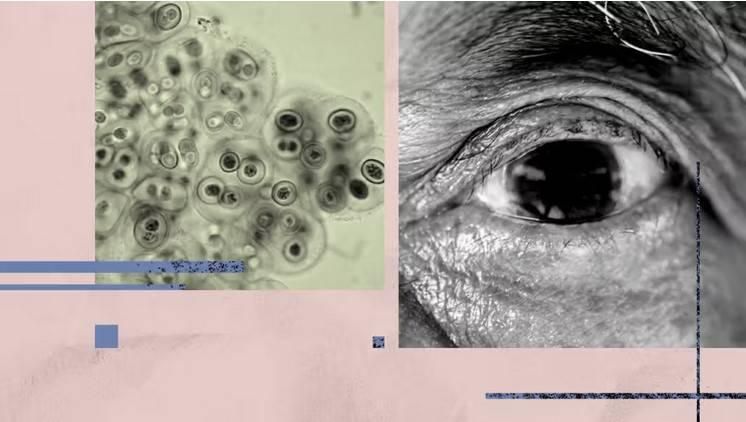

ووفقاً لدراسة نُشرت في مجلة Nature Communications، توصل العلماء إلى أن بكتيريا Chlamydia pneumoniae، المعروفة بتسببها في التهابات الجيوب الأنفية والجهاز التنفسي، قد تبقى في شبكية العين لفترات طويلة، ما يزيد من احتمالات الإصابة بألزهايمر.

وأظهرت نتائج الدراسة أن المصابين بألزهايمر يمتلكون مستويات أعلى بكثير من هذه البكتيريا في أنسجة الشبكية مقارنة بالأشخاص ذوي الإدراك السليم، كما تبين أن ارتفاع مستوى البكتيريا ارتبط بتفاقم التدهور المعرفي.

التهاب عصبي وإنتاج بروتين ضار

وأكد الباحثون أن العدوى بالبكتيريا المذكورة تؤدي إلى زيادة الالتهاب العصبي، وموت الخلايا العصبية، وتحفيز إنتاج بروتين «بيتا أميلويد»، الذي يُعد أحد السمات الرئيسية لمرض ألزهايمر.